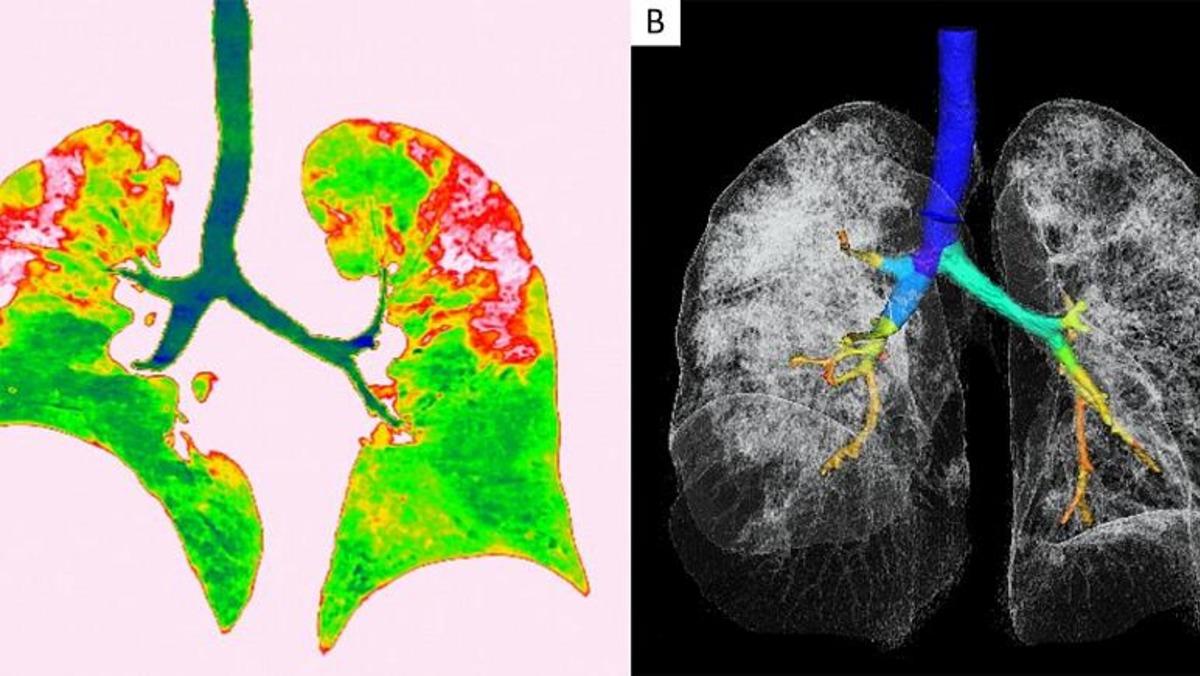

Radyologlar, tomografi görüntüleri sayesinde lezyonların dağılımının daha net anlaşılmasının, virüsü tanıma ve tedavisi için yapılan araştırmalarda önemli olduğunun altını çiziyor.